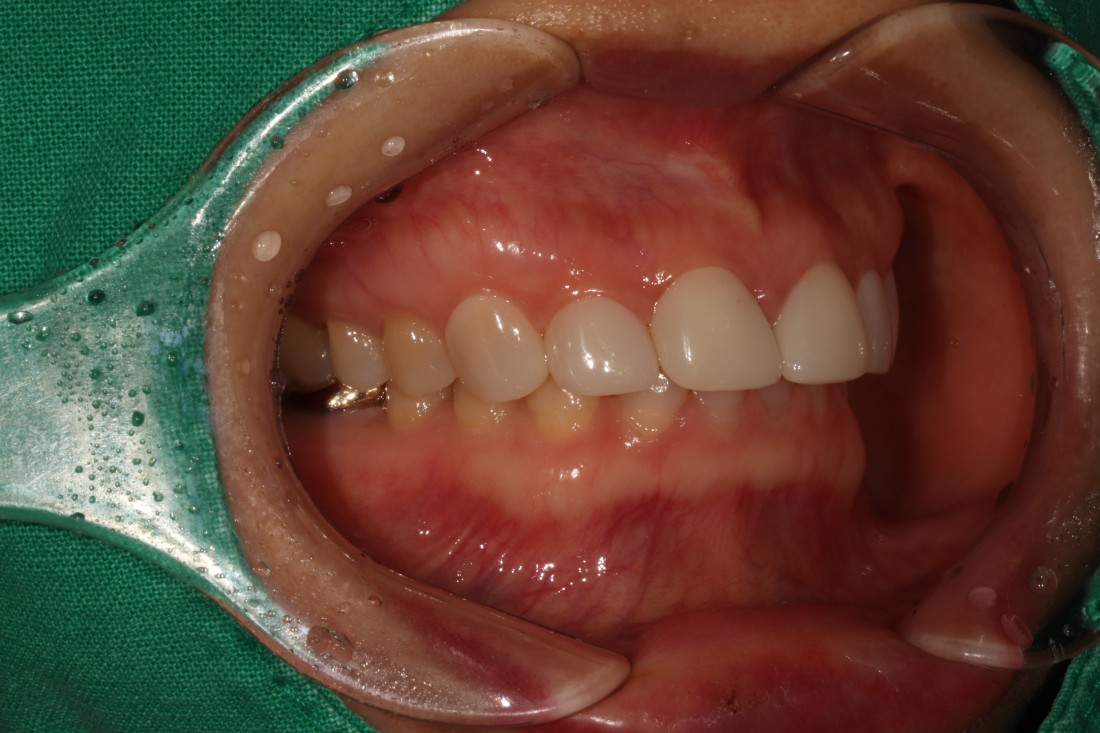

그렇지만 실제로 라미네이트 전/후 사례를

200케이스 가까이 공유하는

라미네이트 치과를 찾기는

쉽지 않은데요.

광주 무삭제 라미네이트 치과는

벌어진 앞니 / 깨진 앞니 /

얼룩덜룩한 앞니 / 왜소치 등

다양한 사례의 라미네이트 전-후 사진을

투명하게 공개하고 있습니다.